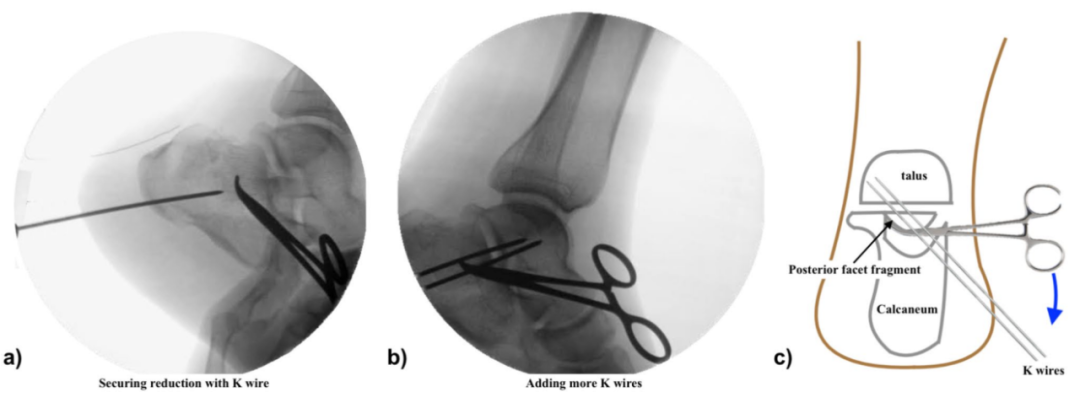

▲图示 a-b 后关节面复位固定后,跟骨结节复位前后的侧位透视片;c 克氏针固定后的侧位透视片;d 跟骨轴向横截面示意图,显示克氏针跨距下关节固定;e 手术切口缝合后的临床照片。

▲图示采用所述经皮技术复位跟骨关节内移位骨折的示例:病例1(a-b)、病例2(c-d)、病例3(e-f)。